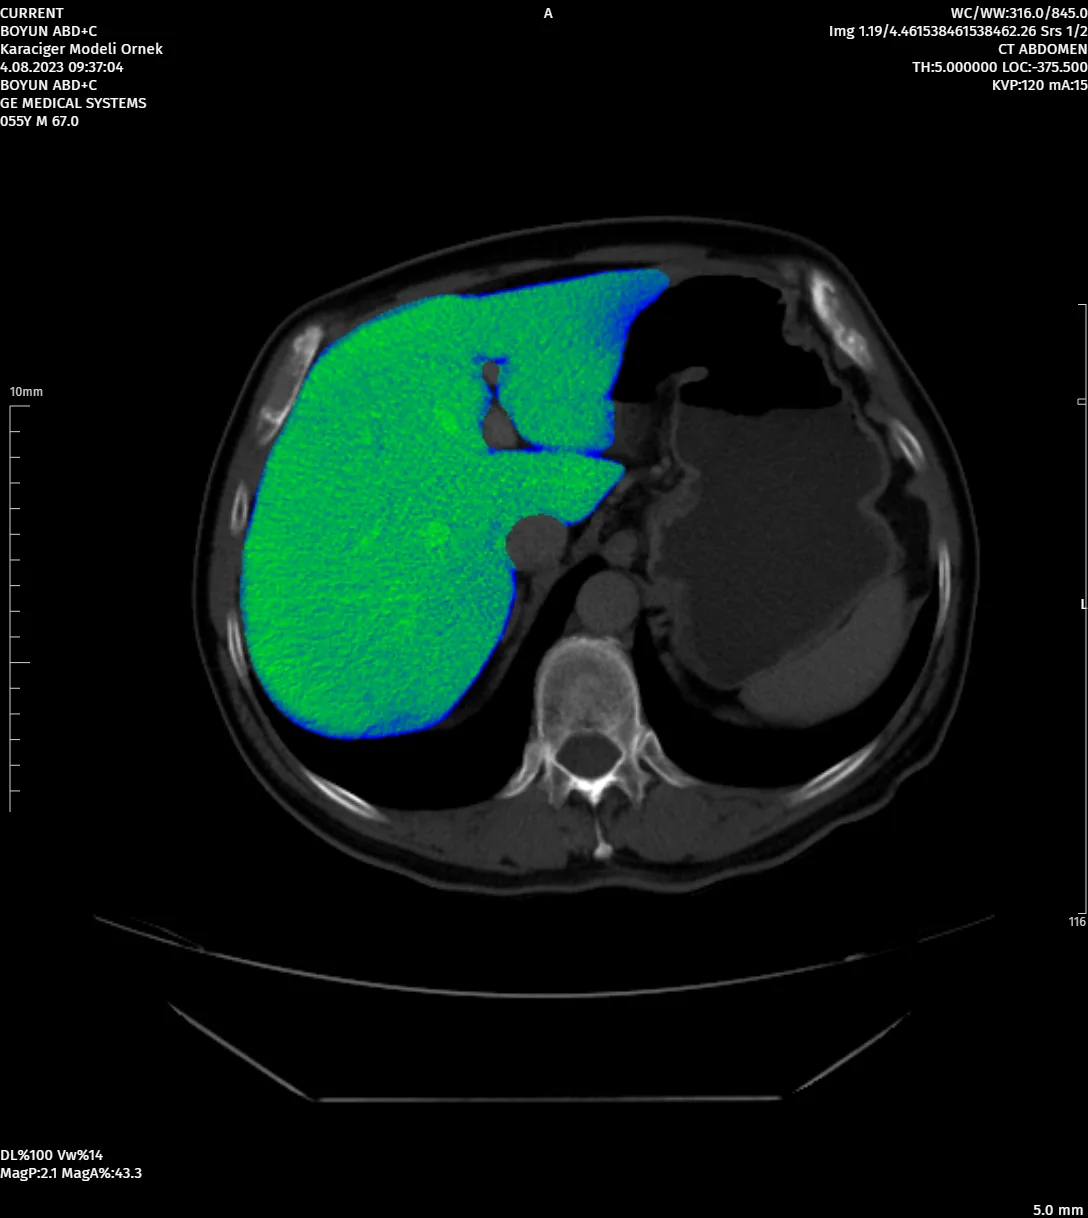

DevamıGelişmiş Görüntü İşleme Araçları

Farklı Segmentasyonlar ile Çalışabilen Görüntü İşleme Araçları